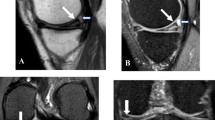

Of the ACLs 13 complete ruptures were accurately diagnosed (Fig. 8). One false-positive diagnosis of chronic tear of the ACL was made (Fig. 9). For the medial meniscus 34 meniscal tears were accurately diagnosed (Fig. 10). There were four false-positive diagnoses of medial meniscal tear (Fig. 11). For the lateral meniscus ten lateral meniscal tears were accurately diagnosed (Fig. 12). There was one false-positive diagnosis of lateral meniscal tear and five false-negative diagnoses (Figs. 13, 14).

Medial meniscal tear, false positive. Sagittal fast proton density image (3,616/12 eff, echo train 8) shows a linear signal consistent with a tear at the junction of the vascularized and nonvascularized portions of the meniscus (arrow). The change was interpreted preoperatively as a menisculo-capsular separation. At arthroscopy, the meniscus appeared intact. There was also an acute ACL tear

Lateral meniscal tear, false positive. Sagittal fast proton density image through the lateral femoral condyle (3,000/12 eff, echo train 8) shows an irregular anterior horn with signal going to the tibial surface (short arrow), called a “complex tear.” At arthroscopy, the meniscus was noted to be “frayed but intact.” Some of the changes around the anterior horn may relate to scarring from the prior arthroscopy portal used for an ACL reconstruction (long arrows)

Lateral meniscal tear, false negative. Sagittal fast proton density image through the lateral femoral condyle (3,200/12 eff, echo train 8) shows an unremarkable lateral meniscus. At arthroscopy, a small radial tear between the anterior and the middle thirds was noted. There was an associated ACL tear

Diagnosis of complete tear of the ACL was satisfactory with one false positive. The interpretation of the single false-positive case may have been influenced by an apparent full-thickness tear of the ACL in that knee on MRI 3 years earlier. Diagnosis of medial meniscal tear was also satisfactory with 34 true positives and four false positives. Three of the four false-positive diagnoses were associated with ACL tear and the changes seen on MRI were in the vascularized portion of the meniscus or at the junction of the vascularized and nonvascularized portions of the meniscus (Fig. 11). In these cases it is possible that the changes were too peripheral for the arthroscopist to visualize, or that the tear had healed prior to arthroscopy. In the fourth case with retrospective analysis the signal went to the tibial surface on only one section and could be considered equivocal for tear.

The sensitivity result for the lateral meniscus was disappointing. Five lateral meniscal tears were missed. It has been noted that associated ACL tear decreases the sensitivity for lateral meniscal tear [8], although only two of the missed tears were associated with this. With retrospective analysis three of the five tears could still not be seen; one was marginal at best; in the fifth case the tear could be visualized but the meniscus was called “frayed” rather than torn. Our arthroscopy numbers are not large, and in particular the numbers for lateral meniscal tear are small as reflected in the wide CIs in the statistical analysis. Whether the low sensitivity reflects problems with interpretation of the tear at the original reading, a particular problem with 3-T imaging for the lateral meniscus, or simply the small numbers cannot be stated with certainty. However, the latter possibility seems most likely.